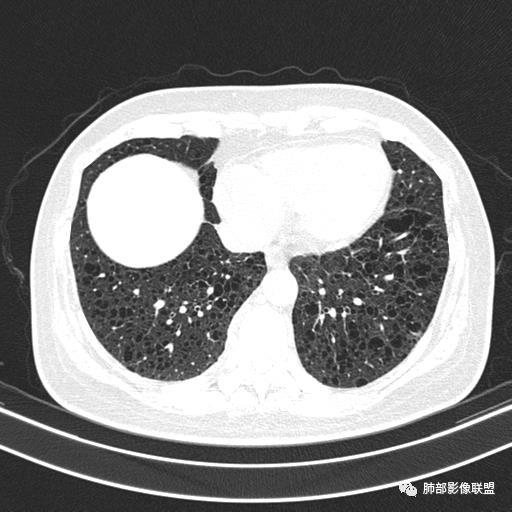

中年女性,不吸烟

双肺弥漫囊腔,累及肋膈角,囊腔形态相对规则单一。

符合LAM

CT平扫示双肺弥漫分布大小不等囊状薄壁透光区,无内、中、外带分布差异,间质稍示增厚。拟LAM

中年女性育龄期妇女,咳嗽气喘,无吸烟史,有苯吸入史。影像:双肺弥漫均匀小囊腔,无明显分布优势,囊腔形态欠规则,壁薄,部分囊腔边缘血管征,伴双肺弥漫磨玻璃影,无结节,考虑lam,鉴别苯中毒肺损伤,囊腔多有分布优势,小叶中心分布为主,形态规整等

女,46,活动性气喘1年。苯吸入史半年。胸部CT:两肺弥漫囊腔,上至肺尖,下至肋膈角,形态类似小囊腔。考虑:LAM,鉴别LIP,BHD,PLCH等。

双肺弥漫大小不一薄壁含气囊腔,囊间肺组织正常,正常肺背景,肺尖肺底受累;青年女性,气喘,支持LAM

双肺多发大小相近的囊状影,分布趋势趋于一致,中年女性,考虑LAM。部分囊内见血管及分隔影,小叶中心性肺气肿代排

CT表现:双肺弥漫大小不等的薄壁囊腔,囊壁<2mm,外形规则,血管影多位于囊腔周围,囊腔之间肺组织正常,随着疾病进展到晚期,囊腔变大、增多,不可胜数,囊腔可融合成较大的囊,与肺气肿相似,形成间质性肺纤维化。部分病例可出现结节影。